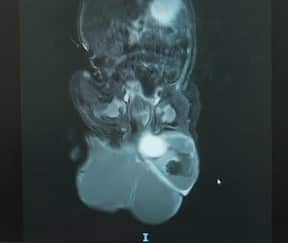

An image of the teratoma growing at the base of Jolie's spine. Source: SBS / Sandra Fulloon

These sacrococcygeal teratomas are more common in female babies and the cause is unknown.

Although Jolie was only 20 weeks old, the tumour was growing rapidly, leading to a range of risks.

Jolie‘s large mass, although not cancerous, could 'steal' crucial blood supply.

"Even though the baby was getting her blood supply through the mum’s placenta, a rapidly enlarging tumour may take more than its share of the blood supply," said Dr Amiria Lynch, director of paediatric surgery at Monash Children's Hospital.

"And that can then affect the growth of vital organs."

"Jolie's teratoma was of a subtype that's called mainly cystic," Lynch explained.

"That meant it was like a water balloon which was filled with fluid.

"So, it wasn’t stealing as much of her blood supply but it was growing so quickly that it was taking up more space."

Jolie's tumour had expanded to around one-third of her body size and was larger than her head.

Dr Amiria Lynch with a scan of Jolie's tumour. Source: SBS / Sandra Fulloon